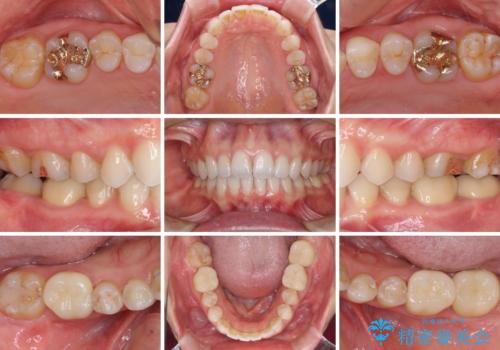

矯正治療後は、奥歯の虫歯や銀歯を補綴・修復治療することとしました。

上顎歯列を下顎に対して4mmほど移動させる必要があったため、治療は長期化することが予想されましたが、患者様にはこちらの期待以上にゴムかけなどに協力いただき、補綴治療も含めて2年強で終えることができました。